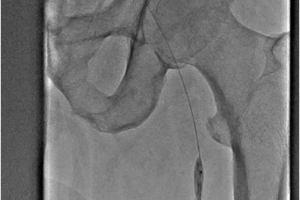

Посттромбофлебитическая болезнь (ПТФБ) развивается у 40-60 % пациентов после перенесенного тромбоза глубоких вен. ПТФБ является одной из разновидностей хронических заболеваний вен нижних конечностей и приводит к трофическим нарушениям. В центре сосудистой хирургии им. Т.Топпера активно занимаются реконструктивной хирургией вен. В настоящее время накоплен большей опыт лечения пациентов с посттромбофлебитической болезнью. Прежде всего это баллонная ангиопластика вен, которая по необходимости может быть дополнена стентированием. На базе нашей клиники вы можете пройти комплексное обследование вен и получить квалифицированную помощь.